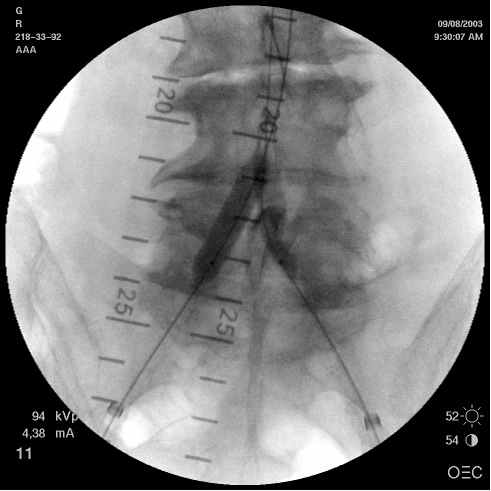

- The pigtail catheter (4-5 F) is used to perform an angiogram the aorta and iliac arteries.Contralateral caudal oblique angulations are very helpful in laying out the common and external iliac arteries. In addition, IVUS interrogation of the vessels may be performed at this time. The length and the diameter of the proximal and distal neck are measured using the angiogram, calibrated catheters or skin markers with or without the IVUS or CT measurements. Based on these measurements and the anatomy, the treatment plan is chosen, that may include balloon angioplasty versus stent grafting (self-expanding vs balloon-expandable vs covered stents).